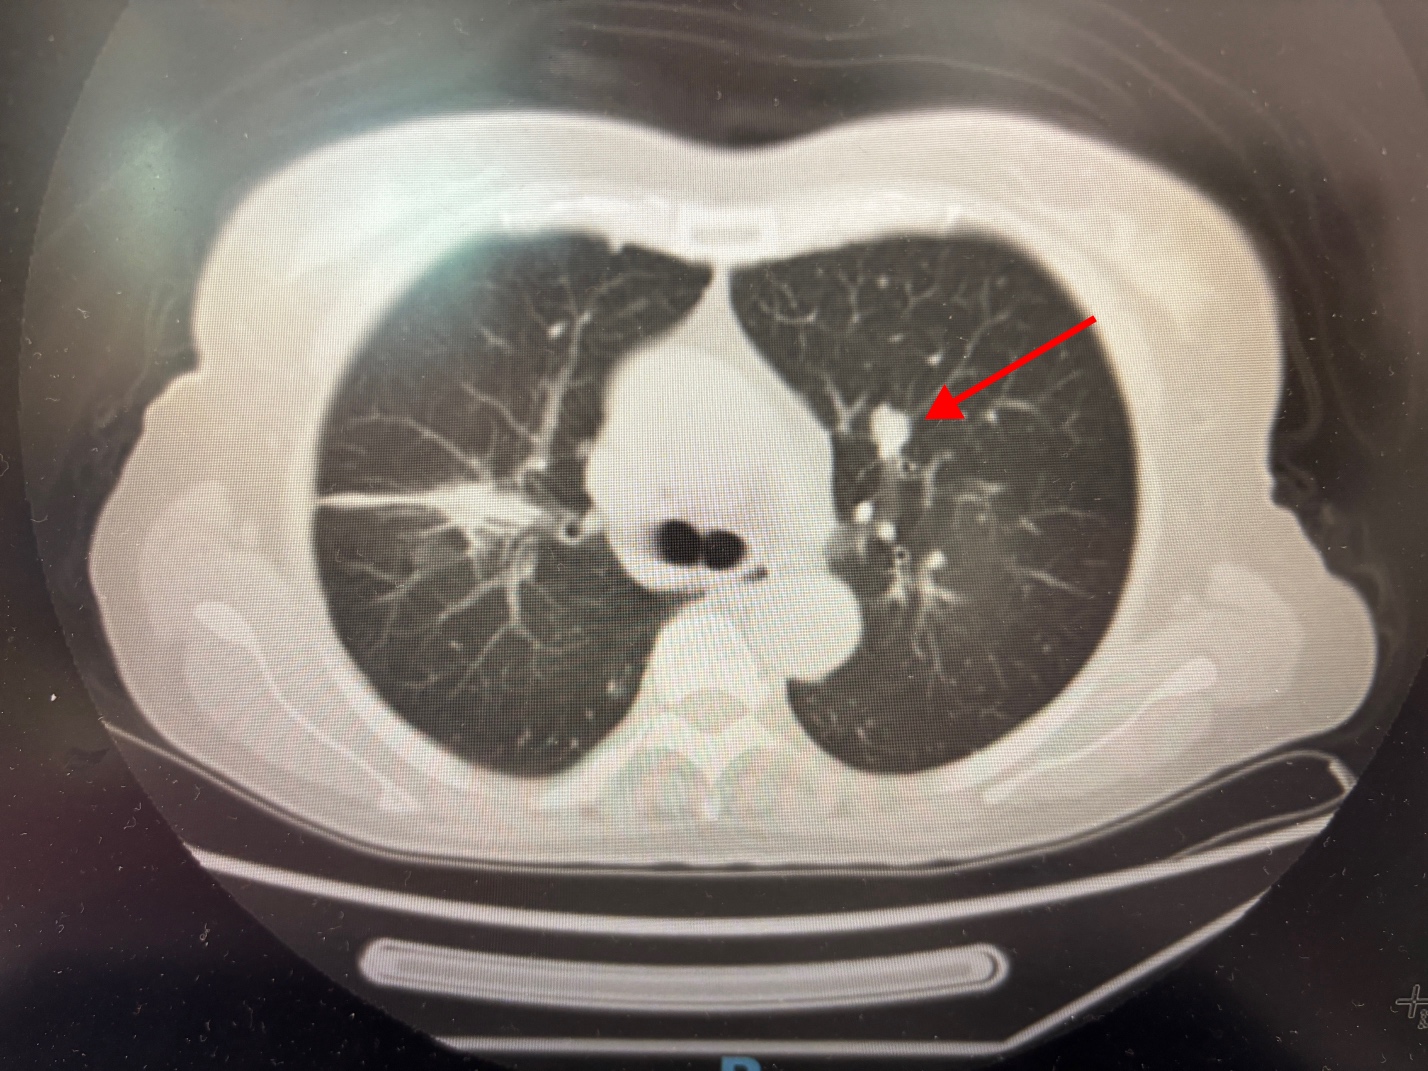

2025.11.22复查,头部稳定,原发肺部1.9*1.3→1.9*1.2cm稳定,但肺多发转移瘤增大0.7*0.6cm→1.1*0.9cm。

谢谢阳光老师建议!每次您的建议都很一针见血,太专业了,我们这个双肺转移瘤确实一直在增大,多发肺转移瘤9月底0.7*0.6cm→11月底1.1*0.9cm  (8月初是0.6*0.5cm,6月中是不足0.5cm)

,可能确实不太适合局部处理了。